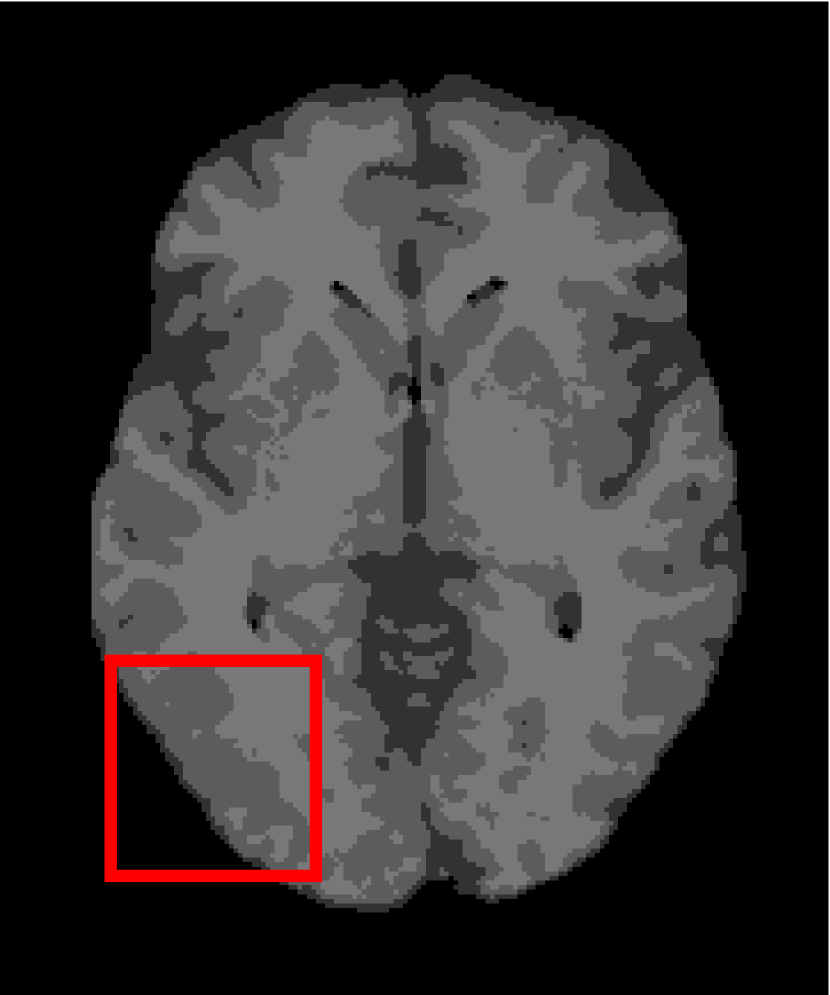

Next, we representatively segment five medical images from BrianWeb. They are represented as five slices in the axial plane with a sequence of 70, 80, 90, 100 and 110, which are generated by T1 modality with slice thickness of 1mm resolution, 9% noise and 20% intensity non-uniformity. Here, we set c=4𝑐4c=4 for all cases. The comparison between WRFCM and its peers are shown in Fig. 9 and Table II. The best values are in bold.

Figure 9: Segmentation results on five medical images. The parameter: ϕ=5.35italic-ϕ5.35\phi=5.35. From top to bottom: noisy images, ground truth, and results of FCM_S1, FCM_S2, FLICM, KWFLICM, FRFCM, WFCM, DSFCM_N, and WRFCM.

By a view of the marked red square in Fig. 9, we find that FCM_S1, FCM_S2, FLICM, KWFLICM and DSFCM_N are vulnerable to noise and intensity non-uniformity. They give rise to the change of topological shapes to some extent. Unlike them, FRFCM and WFCM achieve sufficient noise removal. However, they produce overly smooth contours. Compared with its seven peers, WRFCM can not only suppress noise adequately but also acquire accurate contours. Moreover, it yields the visual result closer to ground truth than its peers. As Table II shows, WRFCM obtains optimal SA, SDS and MCC results for all five medical images. As a conclusion, it outperforms its peers visually and quantitatively.